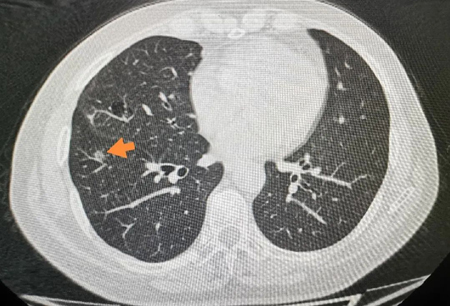

箭头所指即为穿刺针定位最终位置

患者因结核性胸膜炎,胸膜广泛粘连,术中仔细分离粘连带,成功定位到肺部肿物,经胸腔镜肺楔形完整切除以后送病理检测。术后病理显示为微浸润性肺腺癌(最大直径<5mm),患者分期为早期,密切随访。